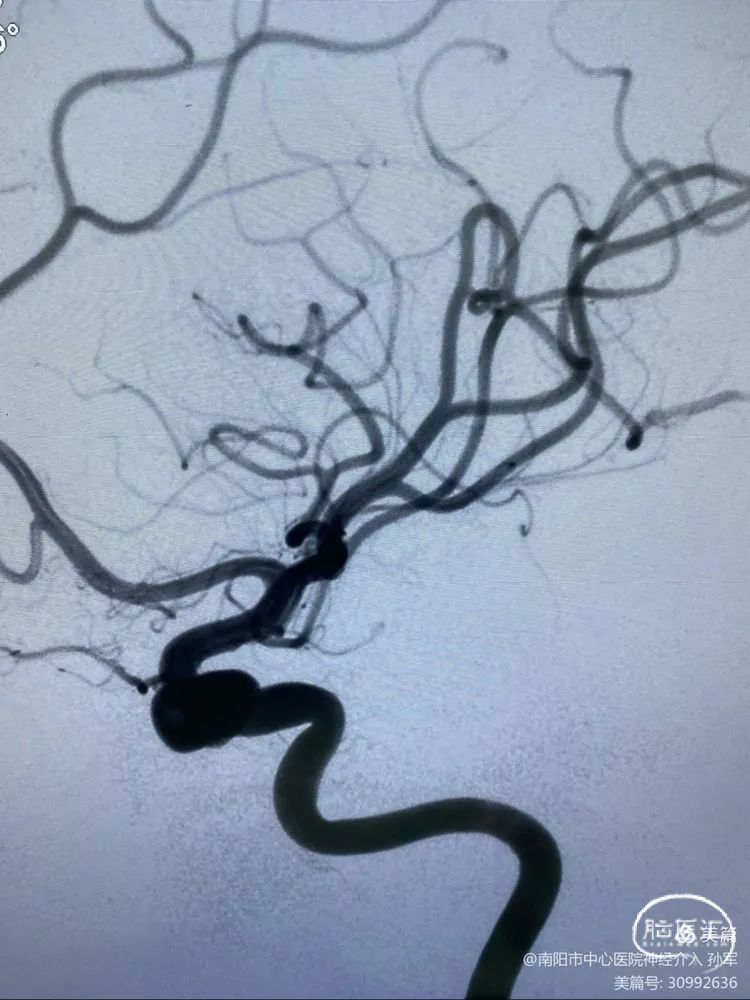

1

7F长鞘内置5F Navien ➕ marksman ➕ Echelon10。

2

到目前一切都顺利。